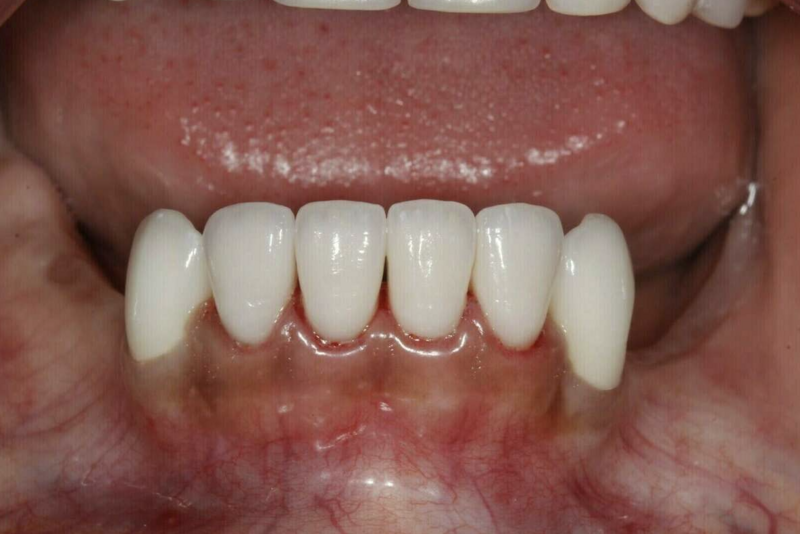

La zircone est une base céramique très dure et résistante qui peut être stratifiées par une céramique plus esthétique et plus tendre : c'est la dentisterie esthétique. La zircone peut être full ou monolithique et est réservée aux dents postérieures car moins esthétique mais plus résistante. La zircone est très biocompatible.

Après

Zircone - traitement au cabinet du Dr COURONNE à Gap

Zircone - cas clinique Dr COURONNE à Gap